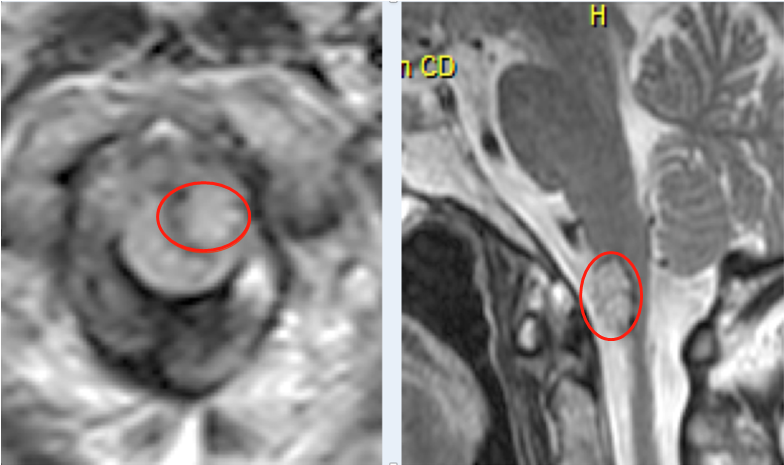

什么是切除程度?切除程度是指去除磁共振圖像上腫瘤體積的程度。有圖有真相,磁共振沒有完成,至少有的不確定性,如果這個不確定性在你身上,你愿意嗎?

對于低級別膠質瘤,特別需要術中或術后72小時內的磁共振進行客觀評價。

切除程度是膠質瘤預后的獨自危險因素。術后殘留腫瘤患者需接受進一步的輔助治療;腫瘤殘留或殘留的臨床評估對后續(xù)治療有重要的指導作用。

較近的研究表明,對膠質瘤切除程度的較客觀評價是術中磁共振(需要在手術室安裝磁共振),明顯優(yōu)于術后72小時。